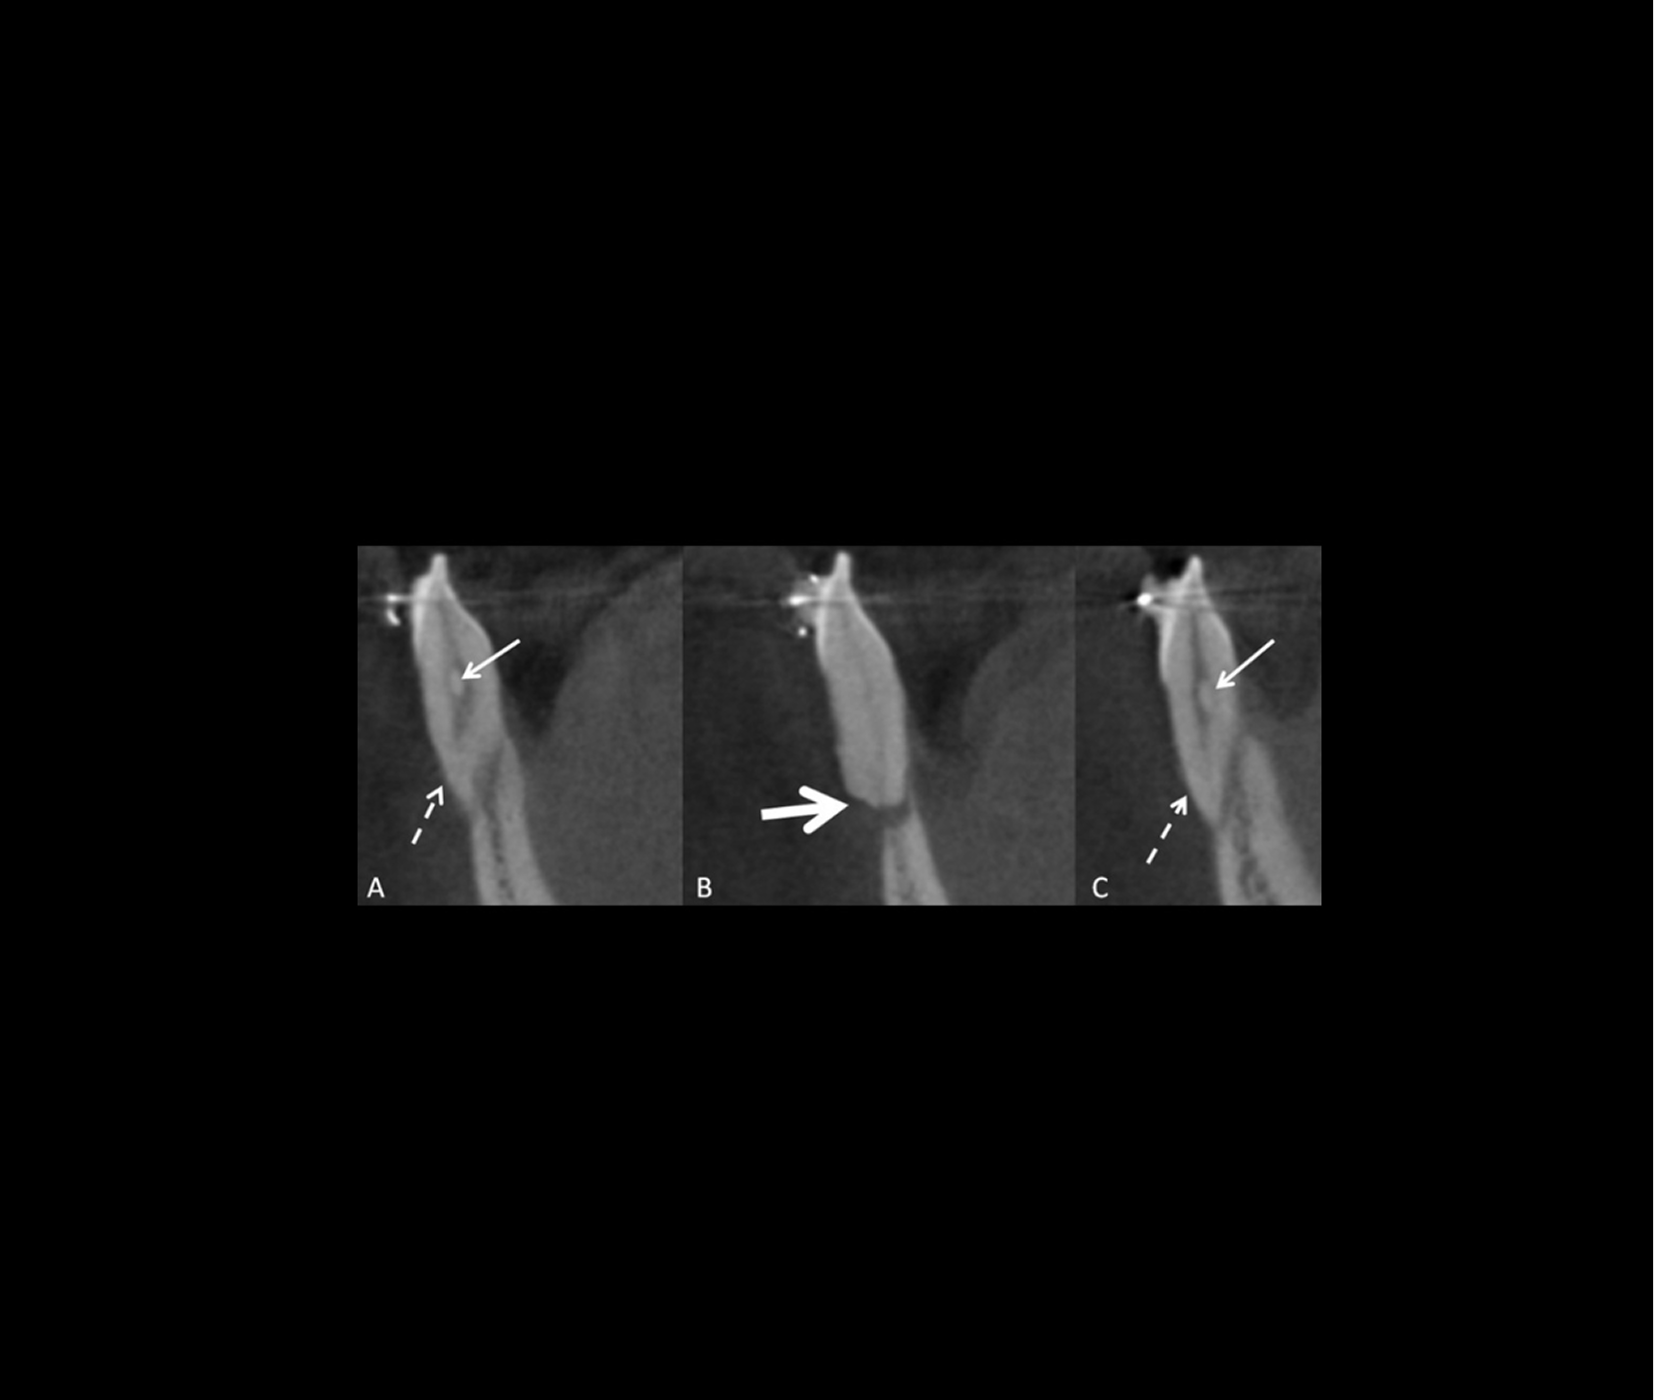

Revue illustrée des principales indications de CBCT en orthodontie